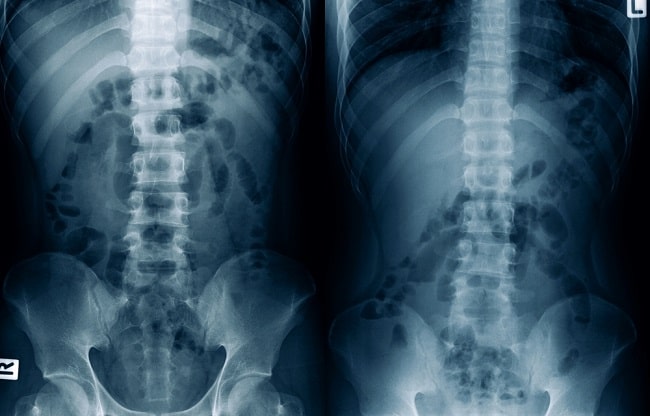

Foto polos abdomen merupakan modalitas pencitraan radiologi noninvasif pada abdomen dengan menggunakan X–ray. Foto polos abdomen digunakan dalam penilaian organ abdomen, seperti saluran pencernaan, ginjal, dinding abdomen, dan tulang.

Foto polos abdomen umumnya dilakukan dengan proyeksi anteroposterior (AP) pada pasien yang berada dalam posisi supinasi. Pada beberapa kondisi, pasien akan diposisikan berdiri atau berbaring pada satu sisi (decubitus) untuk menilai keadaan udara pada abdomen.

Interpretasi foto polos abdomen secara umum terdiri atas pemeriksaan pola udara usus dan udara bebas pada rongga abdomen, pemeriksaan masing–masing organ abdomen untuk melihat adanya kelainan, pencarian adanya kalsifikasi, penilaian tulang, dan penilaian bagian bawah paru.[1–3]